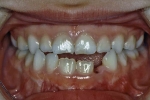

| 初診時